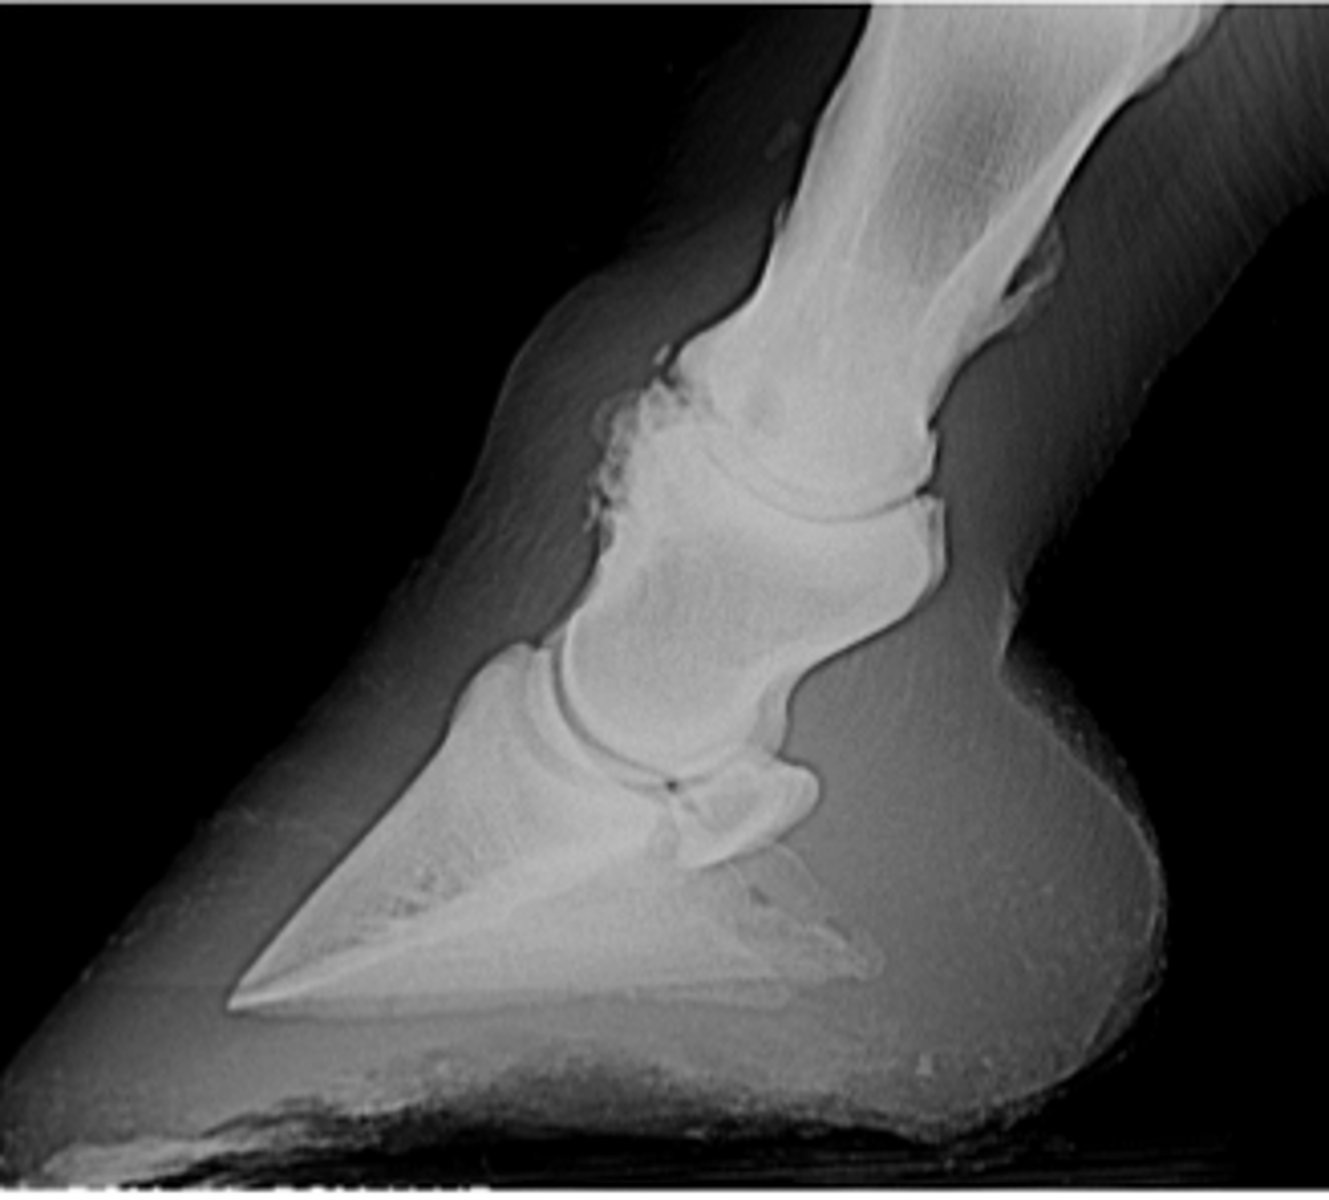

P3

What bone is fractured?

Foot cast

What type of coaptation would you apply for healing?

Suspensory ligament

What structure caused the avulsion?

Remove the middle section of the bone to remove the fracture

How is this fracture treated?